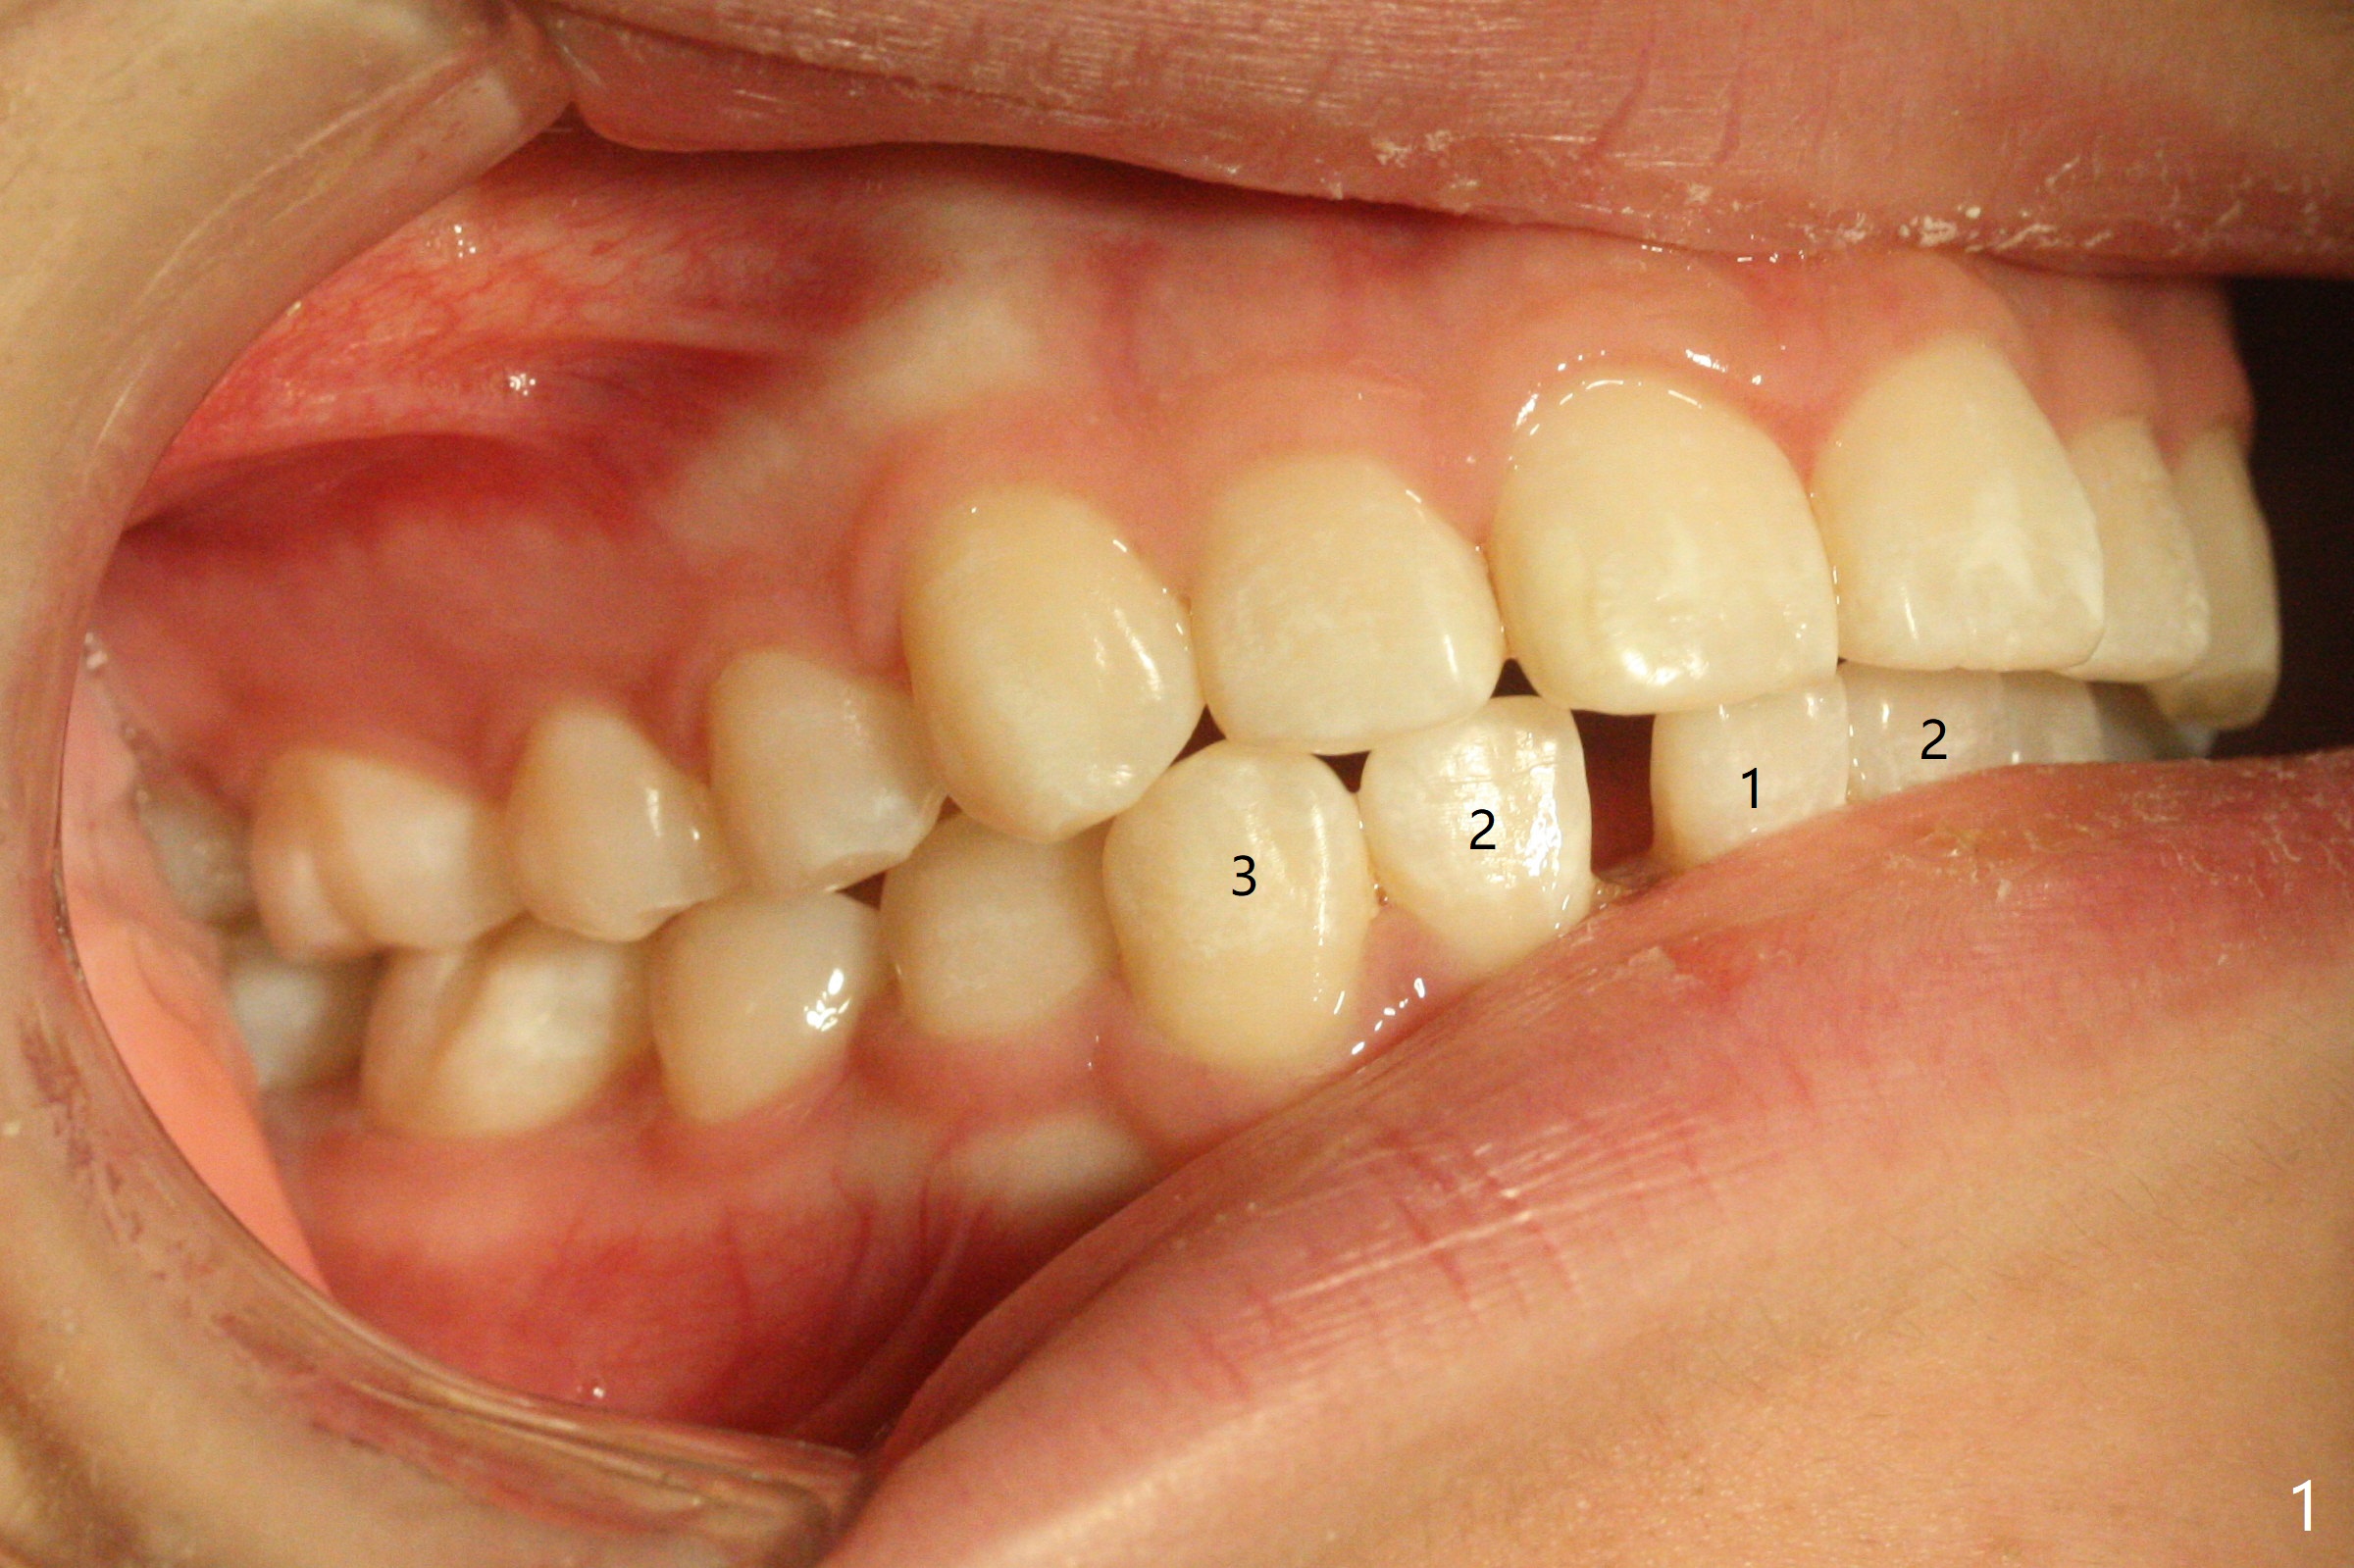

13岁女孩面型正常,先天性缺失右下1(图一,四,七),前牙深覆盖(图二),邻牙扭转(图三),治疗计划使用隐形矫正器,上牙片切,内收,关闭下切牙间隙(图八)。片切前发现上切牙邻面龋(图五,六),最大一个已经修补(右上2),不知其余小的龋坏能否片切,涂氟保守处理?不过她有龋坏易感性,以前乳牙龋坏。邻面片切后,上,下颌分别用无色和蓝色树脂做attachments(图九)。不明白的是Reciprocating saw远不如wheel利索。